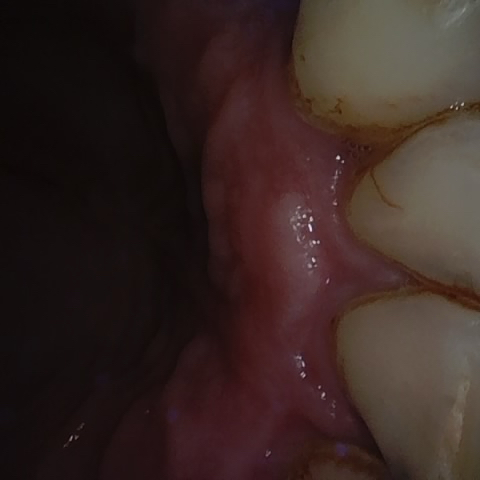

Annotated as "Good"